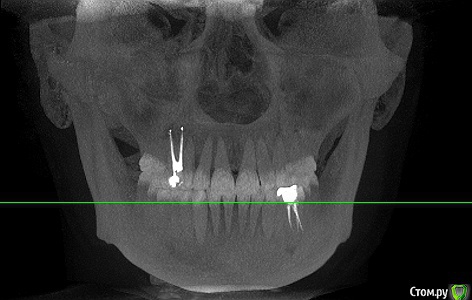

Добрый день! Прошло полгода с момента депульпирования, но ситуация не изменилась.

Неделю назад сделала КТ, по итогам которой на соседнем 15 зубе обнаружен кариес - сразу же его залечили. По 14 зубу ничего не сказали.

Спустя несколько дней после лечения возникла сильная боль во всей правой челюсти. Дома попыталась рассмотреть КТ - кажется, что с зубом 14 все плохо.

Прикрепляю скриншоты КТ. Подскажите, пожалуйста, что это может быть под красной стрелкой на снимках 2 и 3?

post-58215-0-07795200-1573918584_thumb.png

post-58215-0-06349000-1573918592_thumb.png

post-58215-0-59155600-1573918890_thumb.png